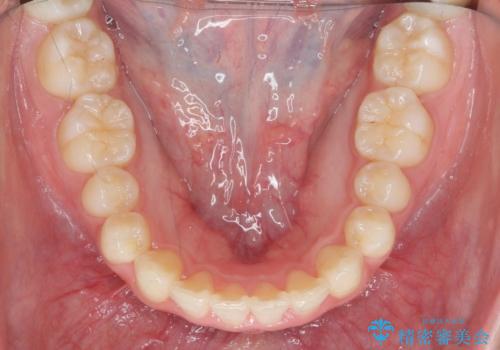

- ねじれの目立つ前歯の見た目を改善したいと矯正治療を希望され来院されました。

がたつきの改善をマウスピース矯正インビザラインで行っていきます。

ガタつきの改善はもちろん、歯列全体のアーチも放物線状にきれいに排列し審美性を向上させることができました。